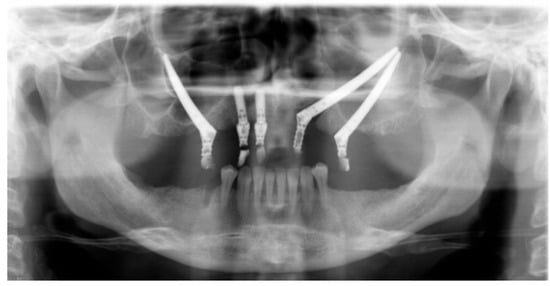

Figure 3.

Panoramic radiograph, showing two ZIs on the left side with their apex in close contact without adequate inter-implant distance.